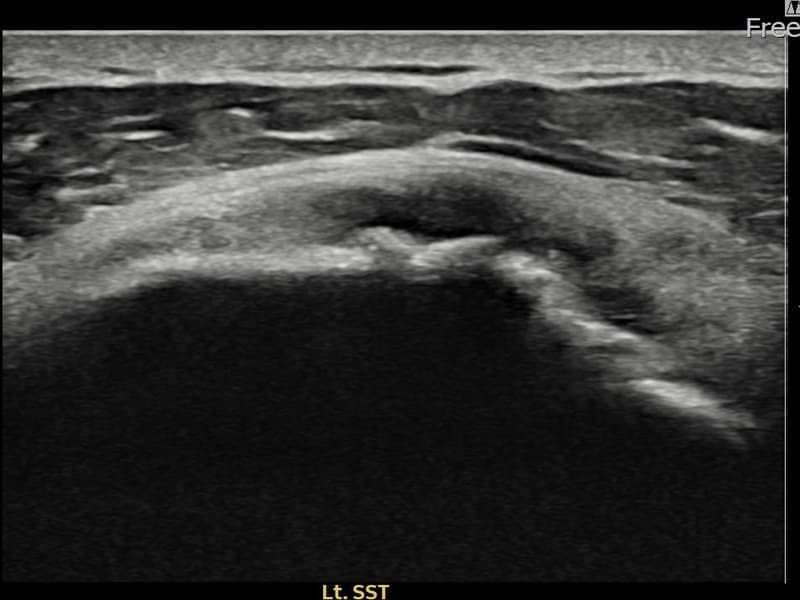

Before

시술 전 초음파 측정 결과 파열 크기는 15mm × 6mm (힘줄 두께의 약 70% 결손)로 확인되었습니다. 시술 전 초음파에서 좌측 극상근건 전층에 걸친 광범위한 에코 단절과 심각한 힘줄 두께 감소가 확인되었습니다. 시술 후 초음파에서 광범위 파열 부위에 재생 조직이 형성되고 힘줄 연속성이 안정적으로 회복된 것이 관찰되었습니다.

50대 중반 남성 환자분으로, 좌측 어깨 광범위 파열로 타 병원에서 수술을 권유받으셨으나 비수술 치료를 원하셔서 내원하셨습니다. 팔을 들어 올리는 것 자체가 매우 힘들고 야간 통증이 극심한 상태였습니다. 정밀 초음파 검사에서 좌측 극상근건의 광범위 부분파열이 확인되었으며, 힘줄 두께가 현저히 감소된 상태였습니다. 파열 범위가 넓어 일반적인 주사 치료로는 회복이 어렵다고 판단하여 초음파 유도 하 축소봉합술을 시행하였습니다. 시술 후 보조기 착용 6주와 단계적 재활 운동을 통해 회복을 진행하였고, 시술 5주 후 추적 초음파에서 광범위 파열 부위의 구조적 안정화와 힘줄 연속성 회복이 확인되었습니다.